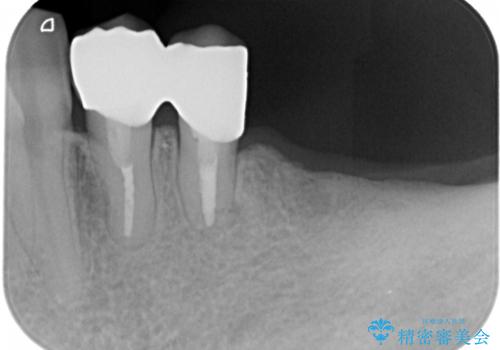

患者様はインプラント等の外科処置は希望されなかったため、セラミックと義歯で治療を行いました。

義歯を製作する際は、支えとなる歯の治療も同時に行うことで、義歯の製作が容易になります。

今回もそのように製作したところ、適合がよく安定のよい義歯になりました。患者様本人も使っていて全く痛くないとのことで、追加の調整もなく使用して頂いてます。患者様には、大変満足して頂きました。